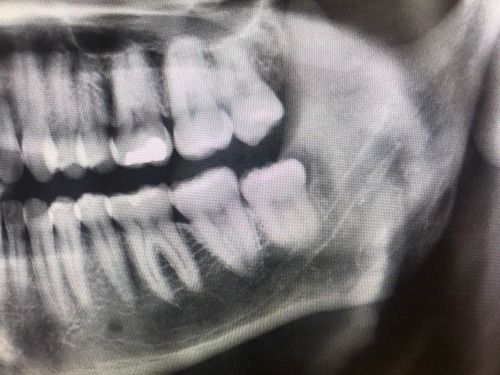

- The maxillary third molar is usually close to the maxillary sinus and can affect the thin bone between the tooth and the sinus. This can result in infection and, rarely, an opening from the sinus into the mouth. An uncomplicated acute maxillary sinusitis usually responds to antibiotic therapy. A chronic opening or chronic sinusitis might require surgical intervention.

Note proximity of third molar root to the maxillary sinus. (Image courtesy Nicolas S. Veaco, D.D.S., M.D., M.S.)